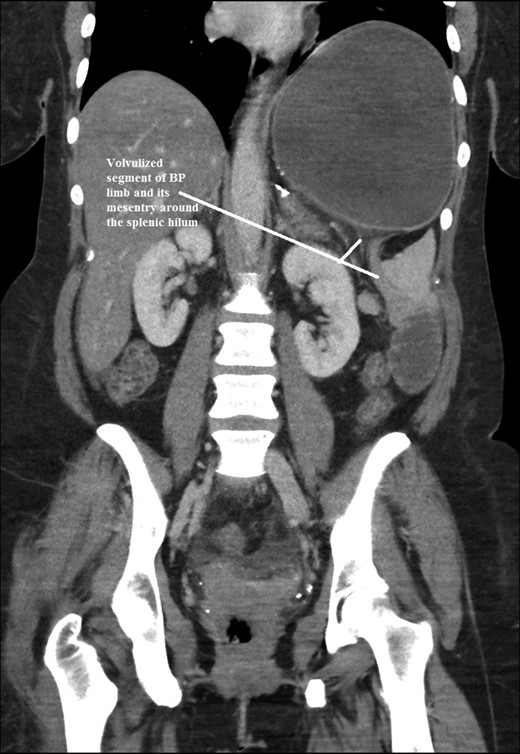

The intraoperative findings were not consistent with the radiological findings (Figs 1–4). As shown in the CT scan of abdomen and pelvis; multiple loops of dilated small bowel were seen, more predominantly dilated and matted bowel complex just above the spleen. The dilated bowel complex was decompressed using needle aspiration to help reduction of the bowel loops. The ileo cecal junction was then identified and traced back to the perisplenic hilar region. The trifurcation of three bowel loops (Roux limb, biliopancreatic limb and common limb) were identified with identification of ligament of Treitz. The prior gastric bypass was of ante colic- ante gastric type and Peterson’s defect was not closed. The above described bowel trifurcation had sunken postero- inferior to the spleen and had herniated through a potential space underneath the spleen and torsed around the splenic vessels and hilum. This picture was consistent with perisplenic small bowel volvulus. As noted earlier there was a massively dilated proximal small bowel segment above the spleen, displacing it caudally. Careful adhesiolysis was performed inferior to the spleen to release the segment of the trifurcation. The bowel segments once reduced were assessed and appeared viable. Of note, the spleen appeared better perfused after reduction. The remnant hernia defect of size 2 × 3 × 2.5 cm around the hilar region was then approximated using interrupted non-absorbable sutures. Enterotomy at the decompression site was closed with non absorbable suture. All potential sites of IH were re-examined and there was no evidence of any other internal herniation. Coelomic cavity was thoroughly irrigated and operation concluded successfully. Postoperative hospital stay was uneventful, and the patient was discharged home after two days.

Coronal CT scan of abdomen and pelvis showing Dilated jejunal segment causing caudad splenic displacement.